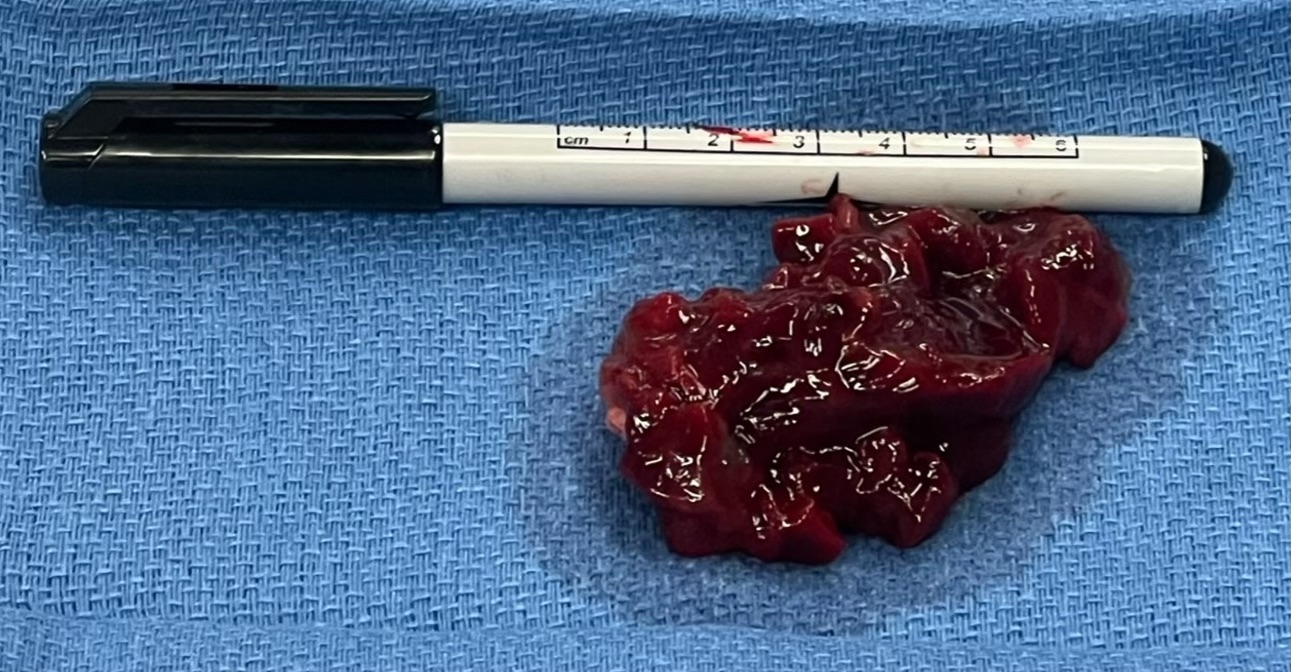

A 44-year-old female with a past medical history of unspecified skin cancer presented with exertional dyspnea for 1 day before admission and syncope 7 months before admission. Physical exam was noted for soft low low-pitched diastolic murmur at the cardiac apex, not appreciated on prior exam. Echocardiography revealed a 3.3x4.7 cm pedunculated, homogenous mass in the left atrium obstructing the mitral valve. Serum BNP was measured as 326. An echocardiogram from less than 29 months prior was reviewed and showed no mass in the left atrium. The patient underwent successful surgical resection of the mass. The mass measured approximately 7x6x2 cm. Histologic analysis reported a proliferation of myxoid stroma with cytologically bland spindle cells positive for calretinin, compatible with cardiac myxoma. Following the surgery, the patient experienced resolution of symptoms.

In this case, we present an unusually fast-growing myxoma in a woman with shortness of breath and syncope. The reported growth rate of atrial myxomas ranges from 1.3 to 6.9 mm a month. Our patient had a negative echocardiogram less than 2.5 years before her presentation, followed by the development of a 7 x 6 x 2 cm mass. Since the onset is unknown, the precise growth rate of our patient's tumor is unknown but was at least 24 mm/month. It is important to consider myxoma in the differential diagnosis of a woman with new onset murmur and syncopal episode. Furthermore, recognizing the potential for rapid expansion is crucial to assessing the risks versus benefits of myxoma section.